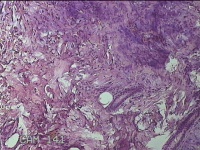

左侧会阴部皮下结节

性别

女

年龄

45岁

临床诊断

皮下结节

一般病史

发现左侧会阴部皮下结节2年余,伴近日局部隐痛不适。

标本名称

大体所见

灰白暗红色结节0.8x0.7x0.3cm一个,表面糜烂。

图2